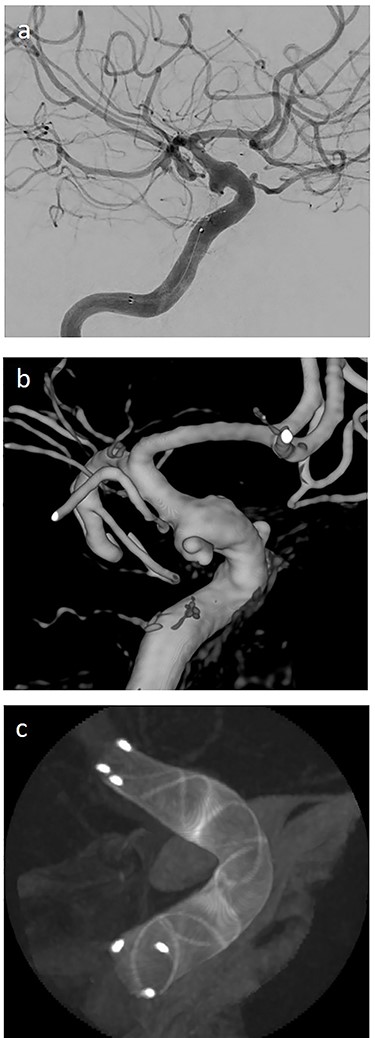

On the next day (Day 9 post-op), the patient suffered from acute and devastating headaches, with screaming and enuresis. An emergency computed tomography (CT) was carried out and displayed a prepontine and retroclival subarachnoid hemorrhage (Hunt & Hess Grade I), (Fig. 2). For further evaluation, a digital subtraction angiography (DSA) was conducted, and it showed a pseudoaneurysm of ophthalmic1/supraclinoid2/C23 part of the left ICA, which was directly treated by a flow diverter (Derivo®—4,5/20), with remaining rest flow (Fig. 3). The patient was transferred to the ICU, transcranial doppler sonography was performed and revealed normal flow. In the following course, the patient suffered from Terson’s syndrome and hyponatremia due to SIADH, but after clinical improvement, was transferred back to normal station after 10 days of post-operative monitoring. Furthermore, the patient was plagued with cephalgia and nausea, which could not be compensated with analgetics and antiemetics. On the 20th post-operative day after the epileptic seizure with postictal vigilance reduction, an emergency CTA was conducted showing progressive SAH (Fig. 4) and a growing pseudoaneurysm as well as generalized vasospasm with posthemorrhagic hydrocephalus. For an emergency CSF diversion, an external ventricle drain was placed. The repeated DSA showed a growing false aneurysm which was treated with two additional flow diverters (2× Derivo®—4,5/20) as well as coiling (HydroSoft™ 2/3 and 2× 1,5/2) by endoleak (Fig. 5). The vasospasms were treated by an intraarterial spasmolysis (Fig. 6).

(a) lateral angiogram of left carotid artery showing ICA aneurysm before the second endovascular treatment; (b) Lateral view after implantation of two additional flow diverters (2× Derivo®—4,5/20); (c) Lateral view after additional coil embolization (HydroSoft™ 2/3 and 2× 1,5/2).